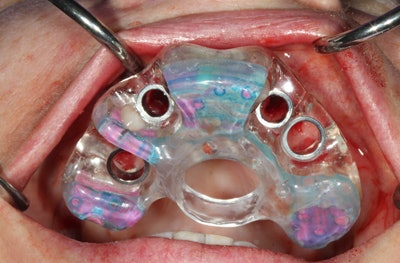

Surgical guides

The use of surgical guides (figure 1) is an absolute necessity to place safe, precise, and optimally positioned implants. With the end in mind, I integrate the data derived from my scan and the dental anatomy derived from my Cerec (Sirona) intraoral optical scan to plan and place prosthetically driven implants (figure 2). Multiple benefits follow this protocol, with the most important being positive patient experiences, faster healing, less postoperative discomfort, and little to no interruption of the patient's daily routine.

Flapless guided implant surgery only requires tissue punch to access the available bone (figures 3 and 4). When ample keratinized tissue is present and sufficient bone volume is present, sutures are unnecessary and the surgery is minimally invasive.

Figure 3: Workflow-guided implant.